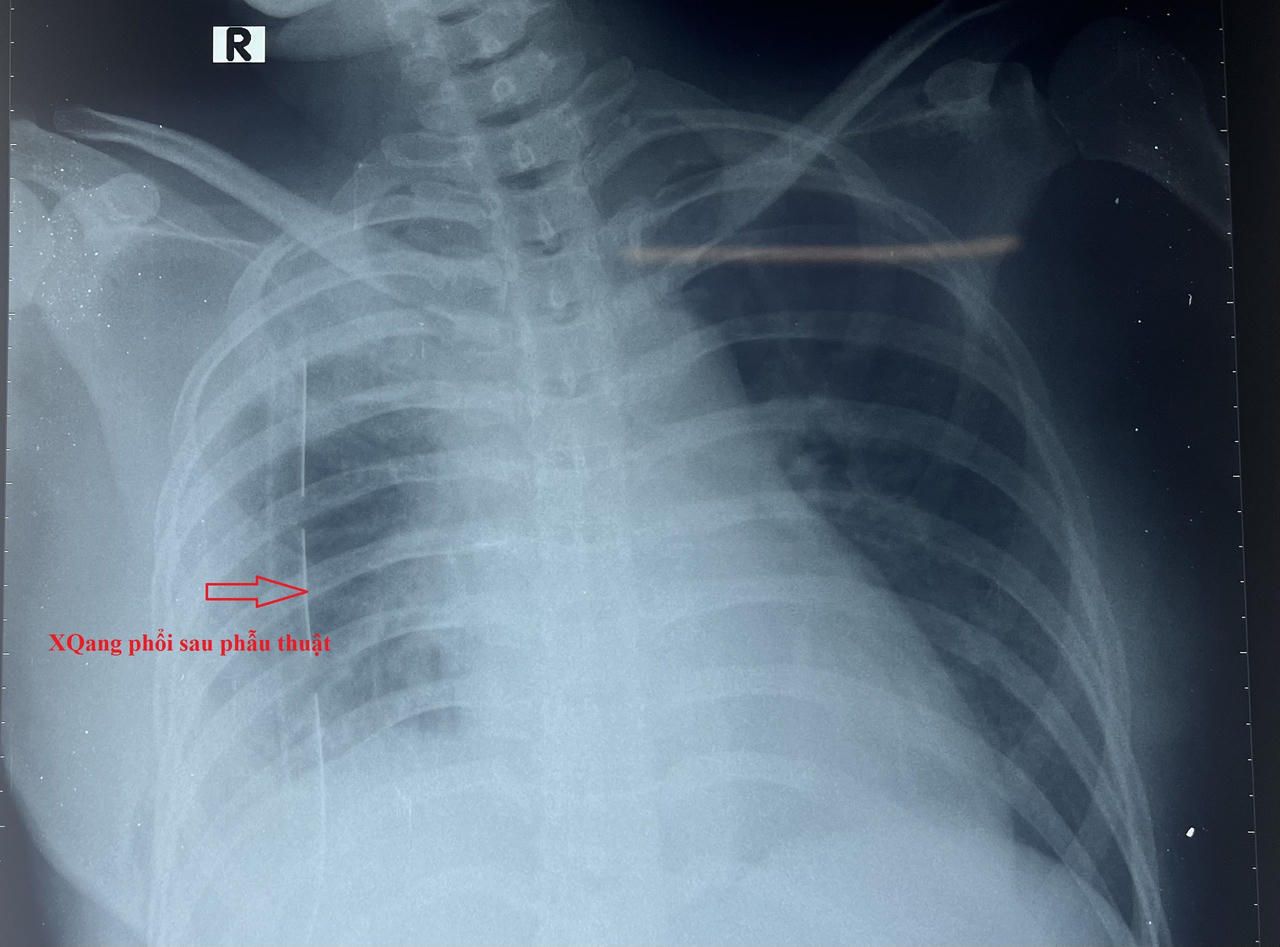

Hình ảnh X-quang ngực sau phẫu thuật |